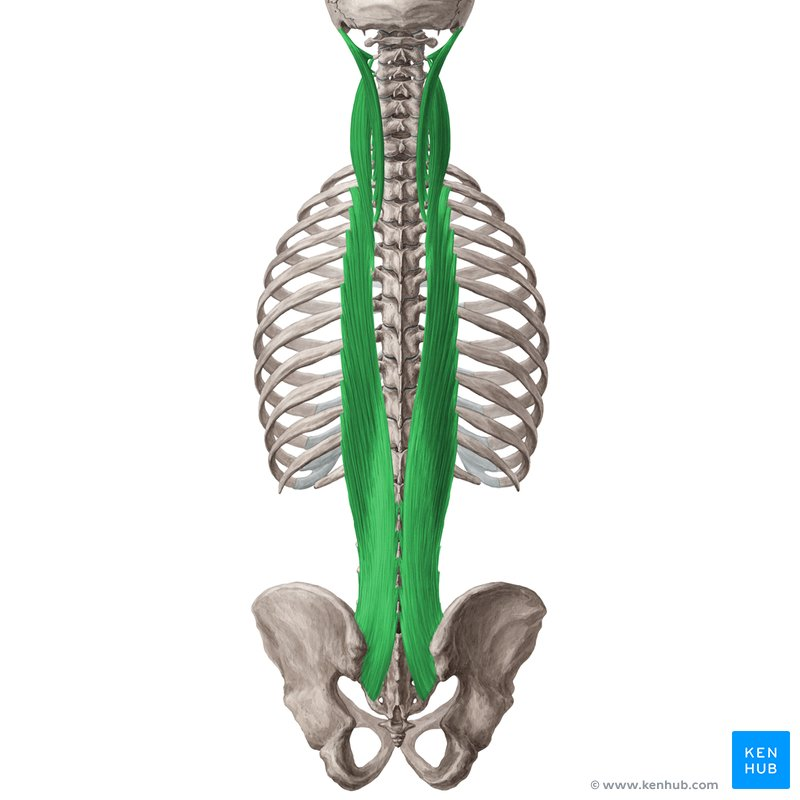

Iliocostalis

Hållning

mm longissimus

Hållning

mm spinalis

Hållning